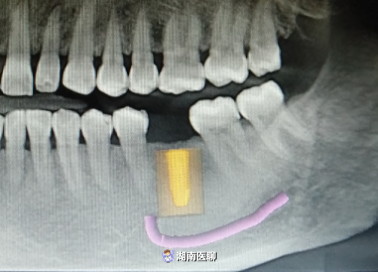

(種植術(shù)前cbct)

(種植術(shù)后cbct)

(術(shù)前種植設(shè)計(jì))

術(shù)后,經(jīng)口腔CBCT檢查,植入的種植體的三維方向都十分契合。